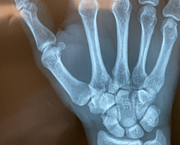

Κάταγμα Σκαφοειδούς Οστού

Το κάταγμα σκαφοειδούς οστού είναι το συχνότερο από τα κατάγματα των οστών του καρπού.  Προκαλείται μετά από πτώση με το χέρι σε υπερέκταση.

Διάγνωση Κατάγματος Σκαφοειδούς Οστού

Απεικονιστικός έλεγχος: Περιλαμβάνει προσθιοπίσθια, πλάγια και την ειδική λήψη σκαφοειδόυς (προσθιοπίσθια με το καρπό σε ωλένια απόκλιση).